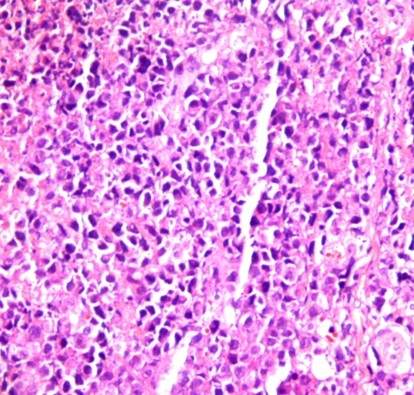

ÇóÖúH&EȾɫºó£¬ »µËÀ¡¢µòÍöϸ°ûµÄÐÎ̬ѧ±ä»¯ ÒÑÓÐ1È˲ÎÓë